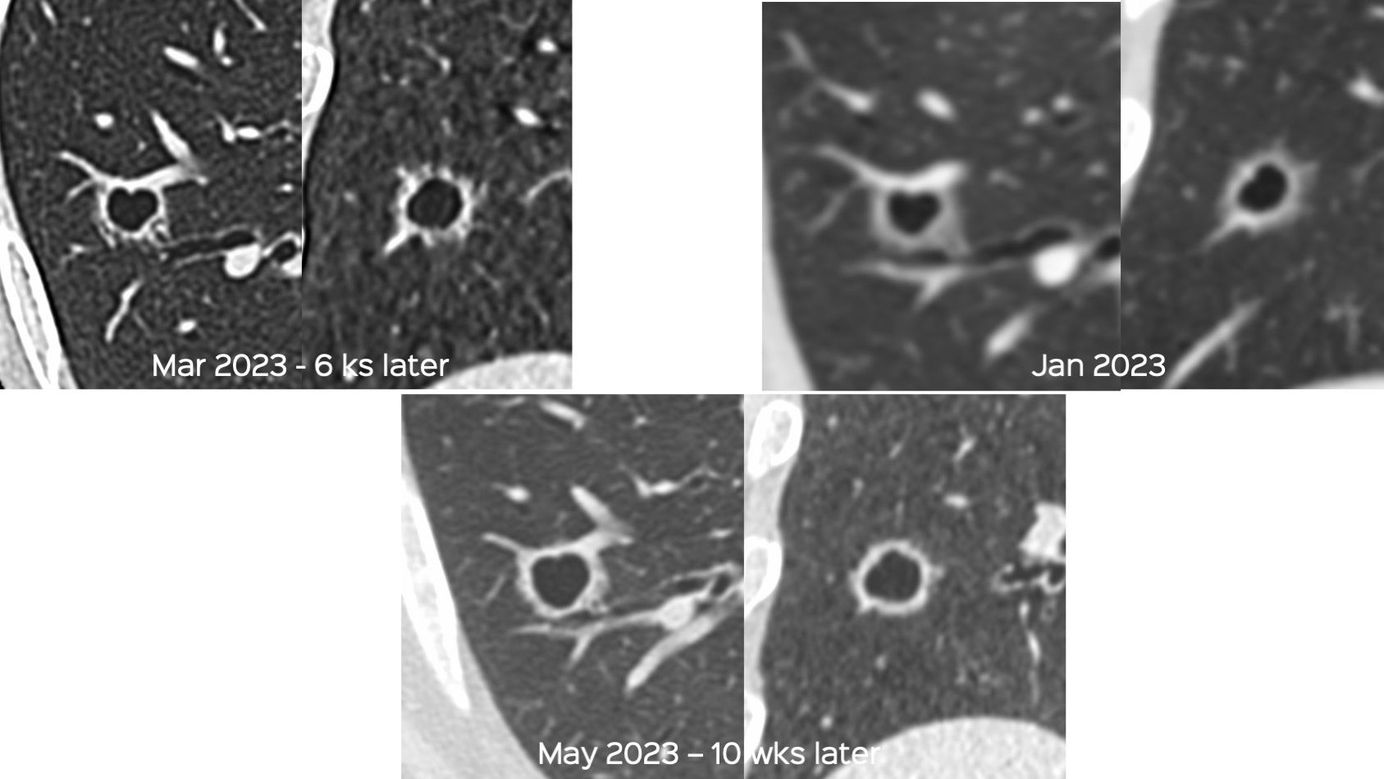

Case 86: A Growing Cavitated Nodule Members Public

Growing lung nodules cannot be ignored and have to be followed-up or biopsied or resected.